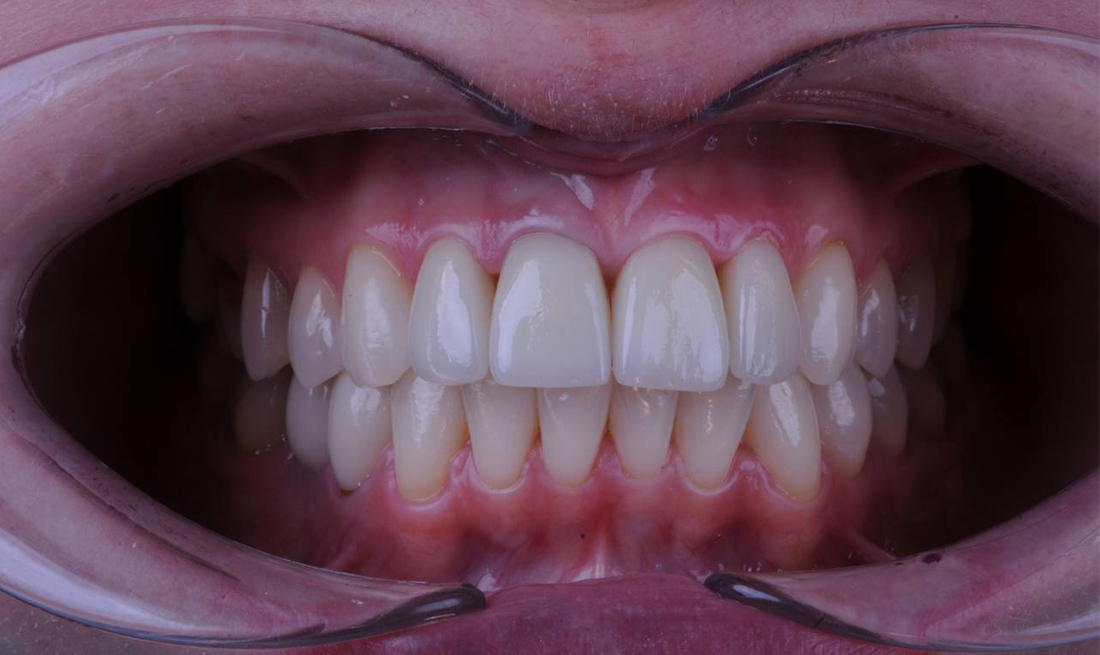

Завершение полной реабилитации – фиксация постоянных циркониевых протезов на 12 имплантах Osstem по методике "Все на 6"